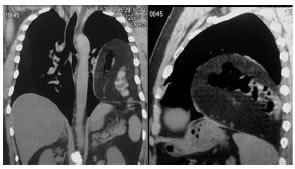

Frente a la sospecha diagnóstica de una hernia diafragmática, se realizó TC de tórax y abdomen.

Descripción de la imagen: Hernia diafragmática izquierda posterolateral con presencia de grasa y tubo digestivo en cavidad torácica.

Discusión: Las hernias diafragmáticas consisten en la migración de estructuras abdominales hacia el tórax a través de un defecto del diafragma. Ellas pueden tener origen congénito (de Morgagni y de Bochdalek) o adquirido, incluyendo las traumáticas y no traumáticas (del hiato, defectos diafragmáticos posteriores). El trauma cerrado y el penetrante constituyen los principales factores etiológicos de las lesiones diafragmáticas. En el 75% de los casos, las lesiones son secundarias a trauma cerrado y en el 25% a trauma penetrante1. Entre el 7% y el 66% de las lesiones diafragmáticas en pacientes politraumatizados no son diagnosticadas2. Las rupturas diafragmáticas son más frecuentes del lado izquierdo (68,5%)3 y esto puede explicarse por: la protección que le da el hígado al hemidiafragma derecho, el subregistro de la lesión y la debilidad del hemidiafragma izquierdo en los puntos de fusión embriológica4. La radiografía de tórax es el método diagnóstico más frecuentemente utilizado en el estudio de los pacientes con trauma de tórax y en el diagnóstico de la ruptura diafragmática aunque sólo se diagnostica el 40% de las lesiones mediante este método1. Los hallazgos característicos de una hernia diafragmática traumática son: presencia de una solución de continuidad diafragmática, herniación de vísceras hacia la cavidad torácica, falta de visualización de un hemidiafragma, zona de estrechez gástrica o intestinal en el sitio de la herniación; el estómago, intestino o tercio superior del hígado están en contacto con los arcos costales posteriores (signo de la víscera dependiente)5. En la mayoría de los casos, puede hacerse el diagnóstico de hernia traumática sólo con las imágenes axiales de TC. Sin embargo, las reconstrucciones multiplanares tanto en los planos sagital como coronal son superiores a las axiales, ya que permiten demostrar pequeñas lesiones.